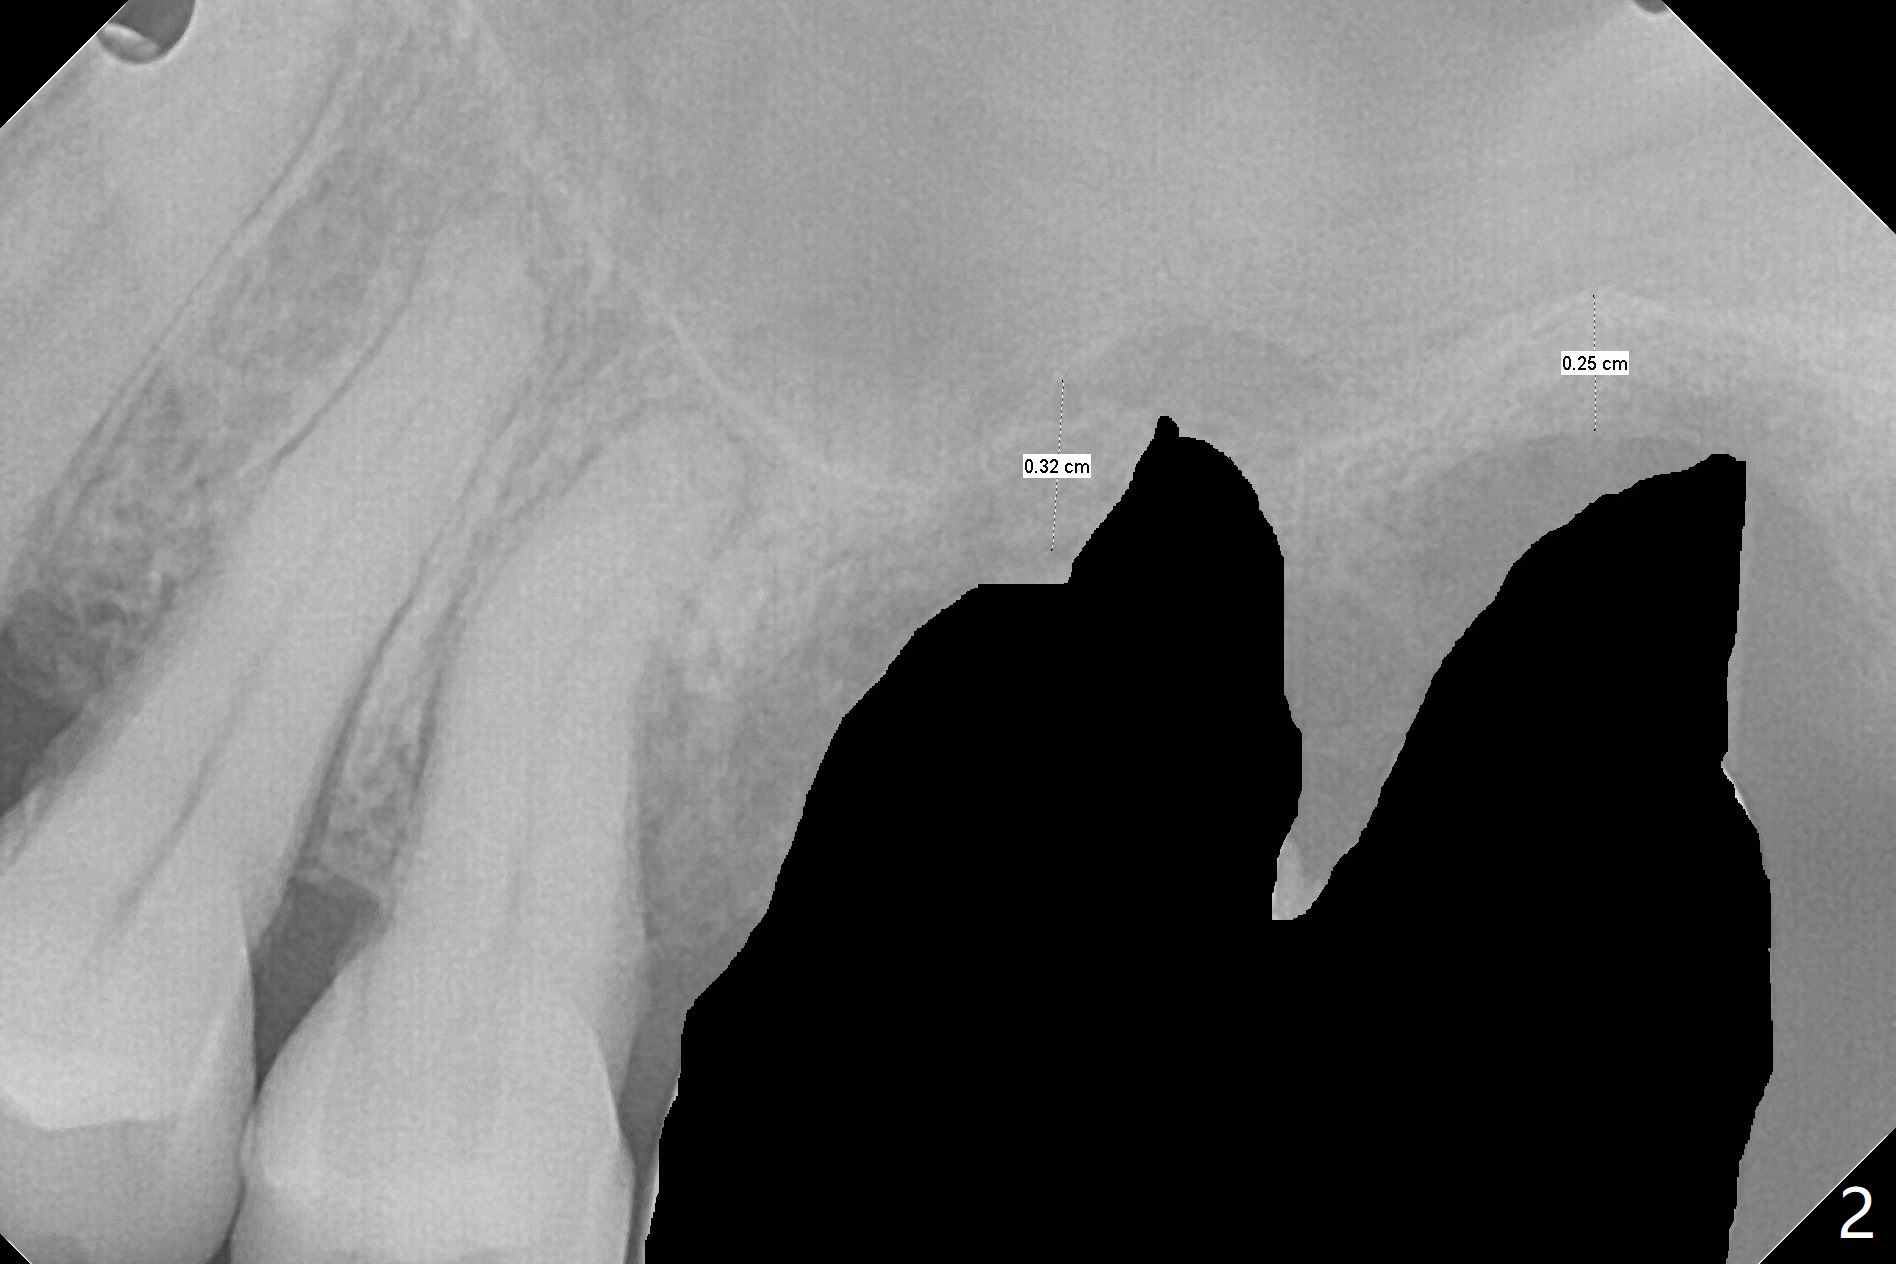

54岁女左上6,7连冠松动,牙槽窝大而敞开,似乎只有即刻植牙即刻修复能够固定粘性骨粉(抽血x2,图三),残余骨壁很薄(2-3 mm,图二),上颌窦内提升应该容易,使用Magic Sinus Lift Kit,其实6腭侧根可能已经进入上颌窦(图一:*)。两张PRF膜当中剪个洞,放置植体开口,然后插入基台,膜周围与牙槽窝开口接触,牙龈下1-2毫米,在膜下面再放置适当骨粉,膜表面放置湿纱布(防止树脂与膜粘合),然后制作临时牙冠。